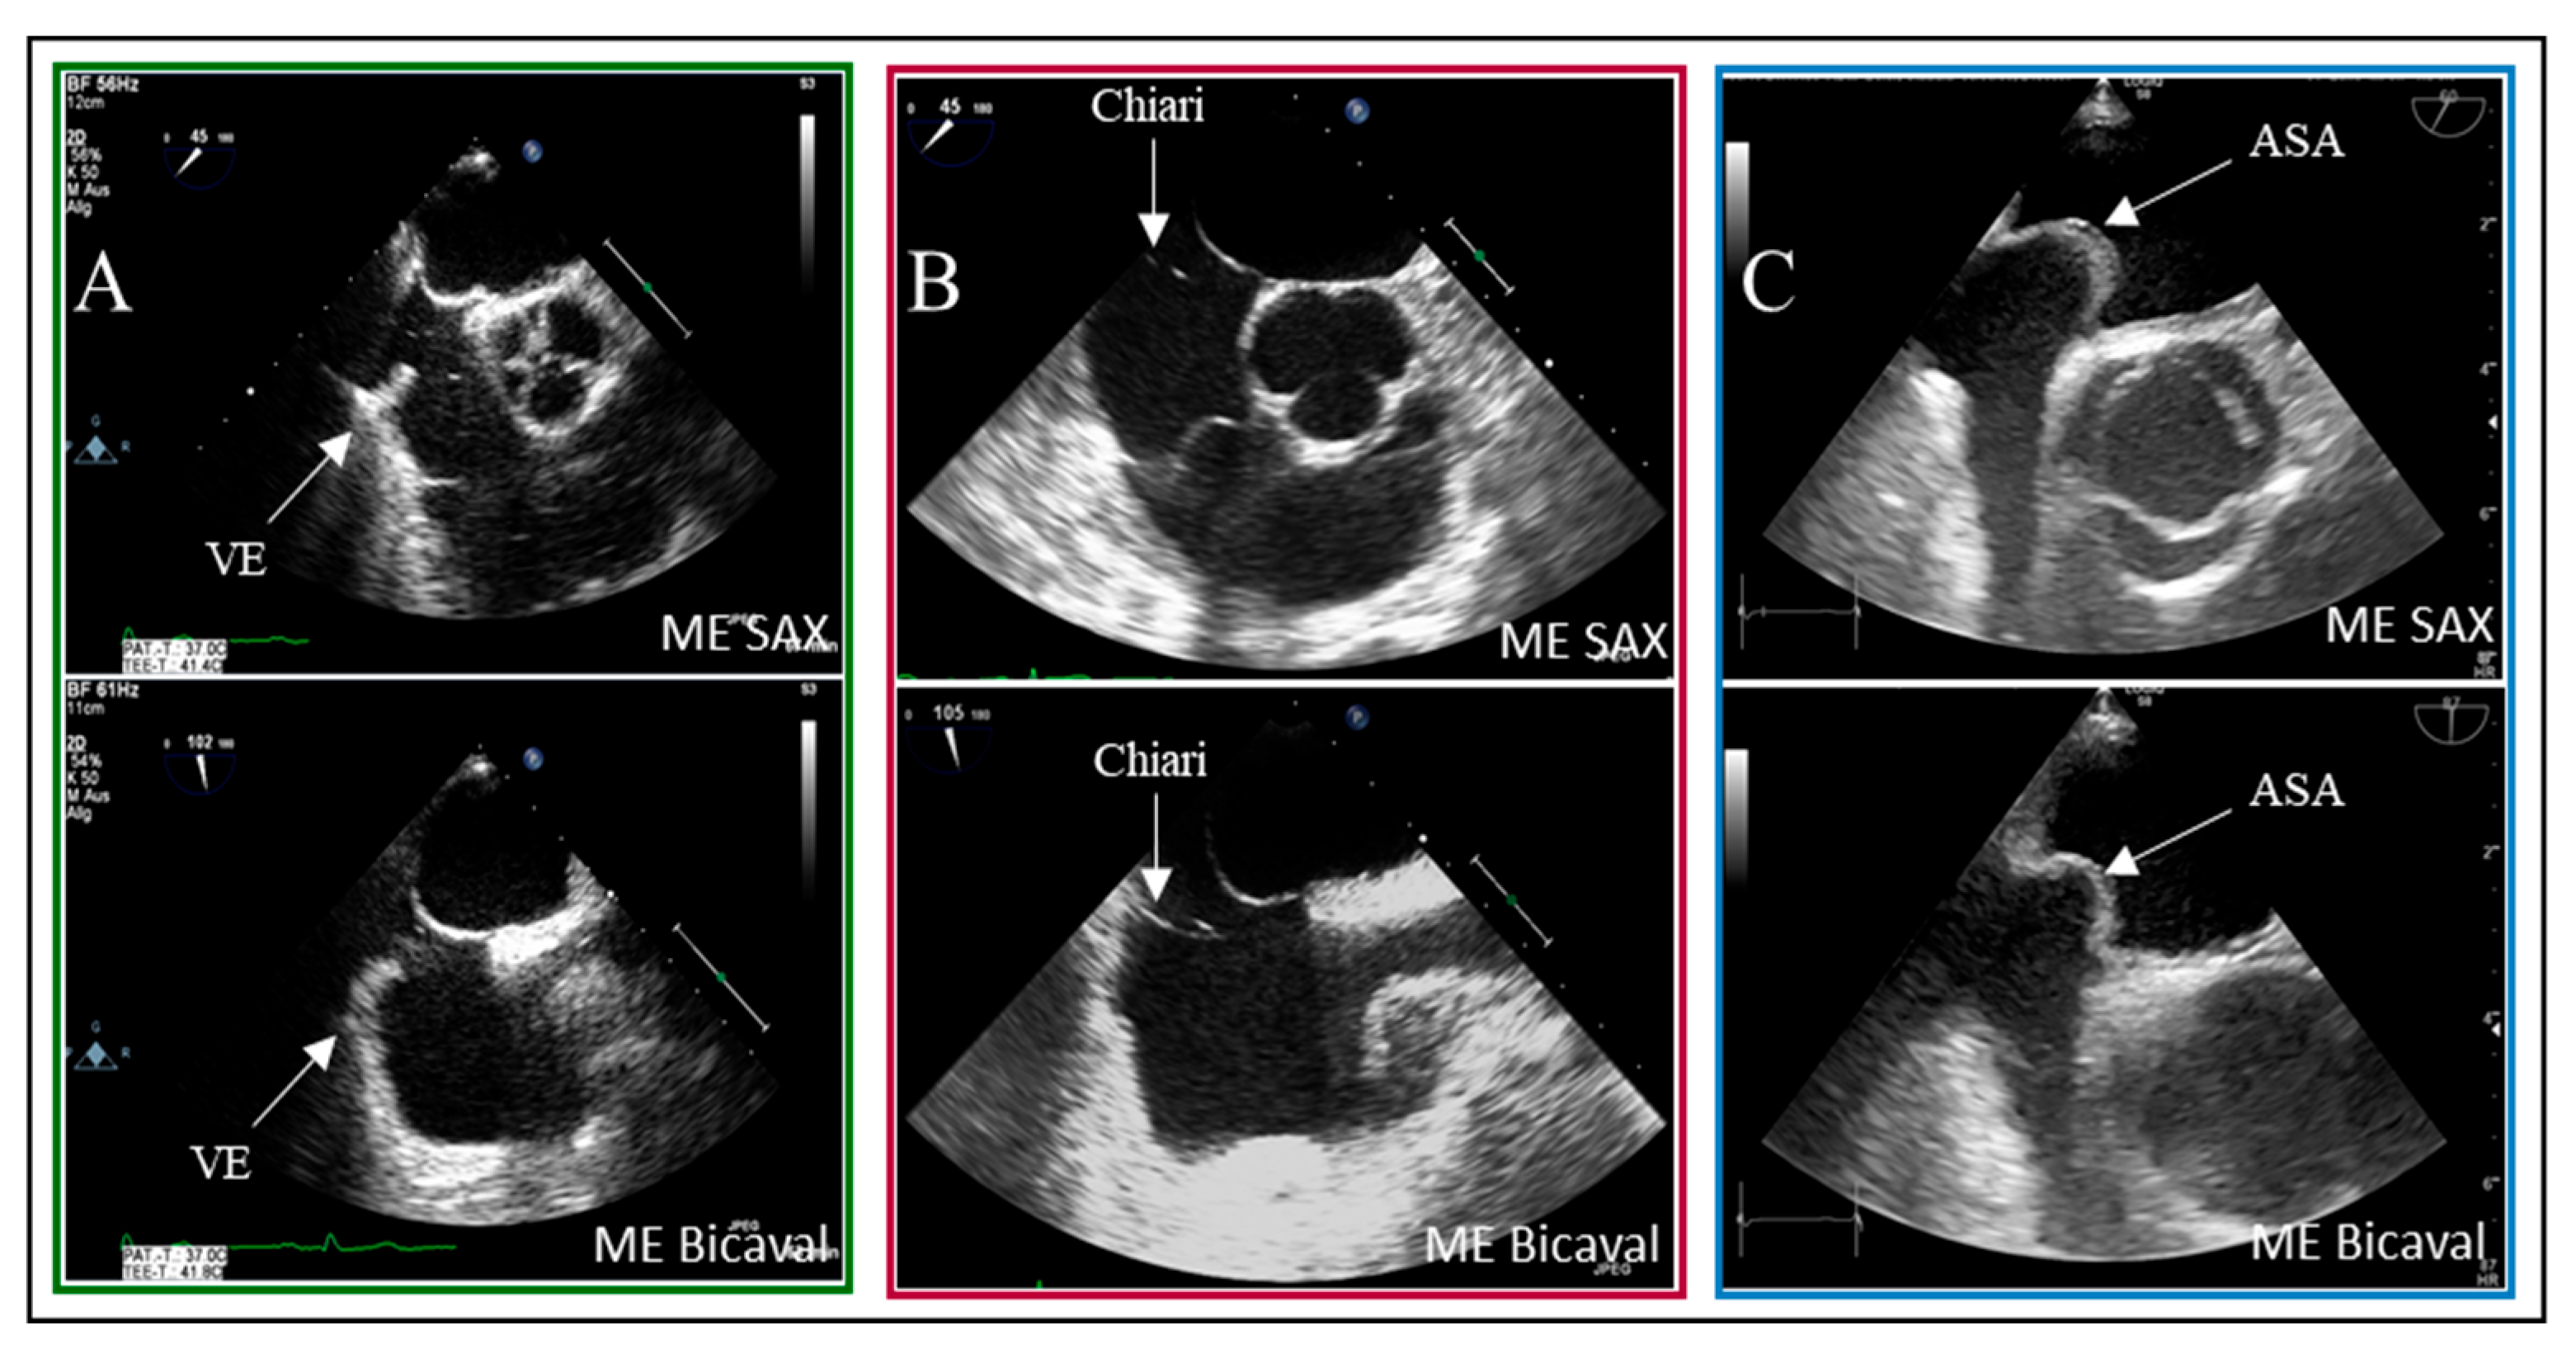

Examples of residual fetal structures are shown in Figure 4.

Figure 4. Two-dimensional TOE recordings of fetal anatomical structures as risk factors for PFO. Shown in the ME SAX and ME Bicaval views are (A) a Eustachian valve at the ostium of the inferior vena cava, (B) a Chiari network as a ribbon, fenestrated membrane in the right atrium, and (C) an atrial septal aneurysm with a protrusion into the right and left atrium. VE: Valvula Eustachii, ASA: Atriales Septumaneurysma, ME: Midesophageal, SAX: short axis.

In eleven of the 20 false-positive PFO diagnosis cases, spontaneous contrast was observed in the left atrium (LA). The timing of microbubble appearance in LA serves as a general guideline but is not a reliable indicator. According to Soliman et al., there is significant temporal overlap in the occurrence of bubbles in LA from both a PFO and a proximal interpulmonary shunt [19]. As illustrated, the presence of interatrial septum (IAS) hypermobility significantly influences the timing of bubble crossover. Delayed crossing may result from residual fetal structures in the right atrium, such as the Eustachian valve and the Chiari network. In 5% of patients with PFO, bubbles were detected in LA after six heartbeats.

This analysis revealed a statistical association between high-grade shunt intensity and PFO diagnosis in the context of IAS hypermobility (p = 0.02). In contrast, remnants of fetal circulation did not significantly impact shunt flow intensity. However, delayed contrast filling of the right atrium remains visible in the imaging sequences, which is critical for the bubble test, as indicated by Johansson et al. [15].